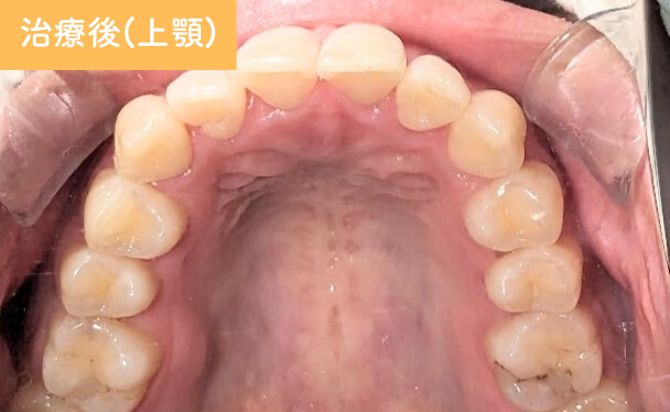

歯並びの変化(上)

治療終了時には、患者様が気にされていた上顎1番の突出が軽減され、前歯の位置が適正化しました。上顎2番の舌側傾斜も改善され、左右のバランスが整った歯列アーチが得られています。